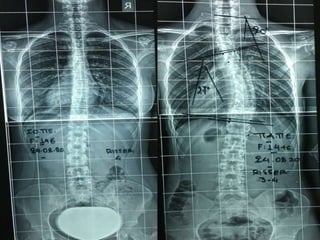

Double Spinal Deformity: a) Idiopathic

adolescent scoliosis

b) Spondylolysis - spondylolisthesis

Post operative correction